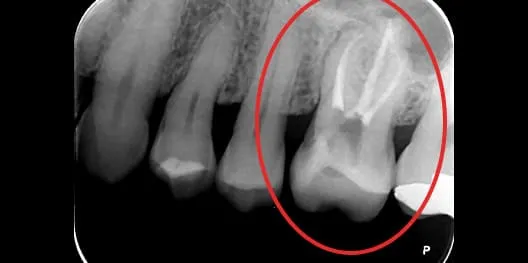

治療前 治療前

治療後 治療後

抜髄の症例

主訴

2日前から夜も眠れないほどの痛みがある

治療内容

抜髄

年齢

50歳

治療期間

3週間(治療回数は2回)

治療費用

¥132,000+再診料¥3,300(税込)

治療のメリット

・感染源を除去し、症状の改善が期待できる

・歯を保存し、抜歯を回避できる可能性がある

・咬合機能の維持につながる

・適切な処置により、長期的な安定が期待できる

リスク・副作用

・術後に疼痛や違和感が生じることがある

・感染の残存や再感染により再治療が必要となる場合がある

・歯質の減少により破折リスクが高まる可能性がある